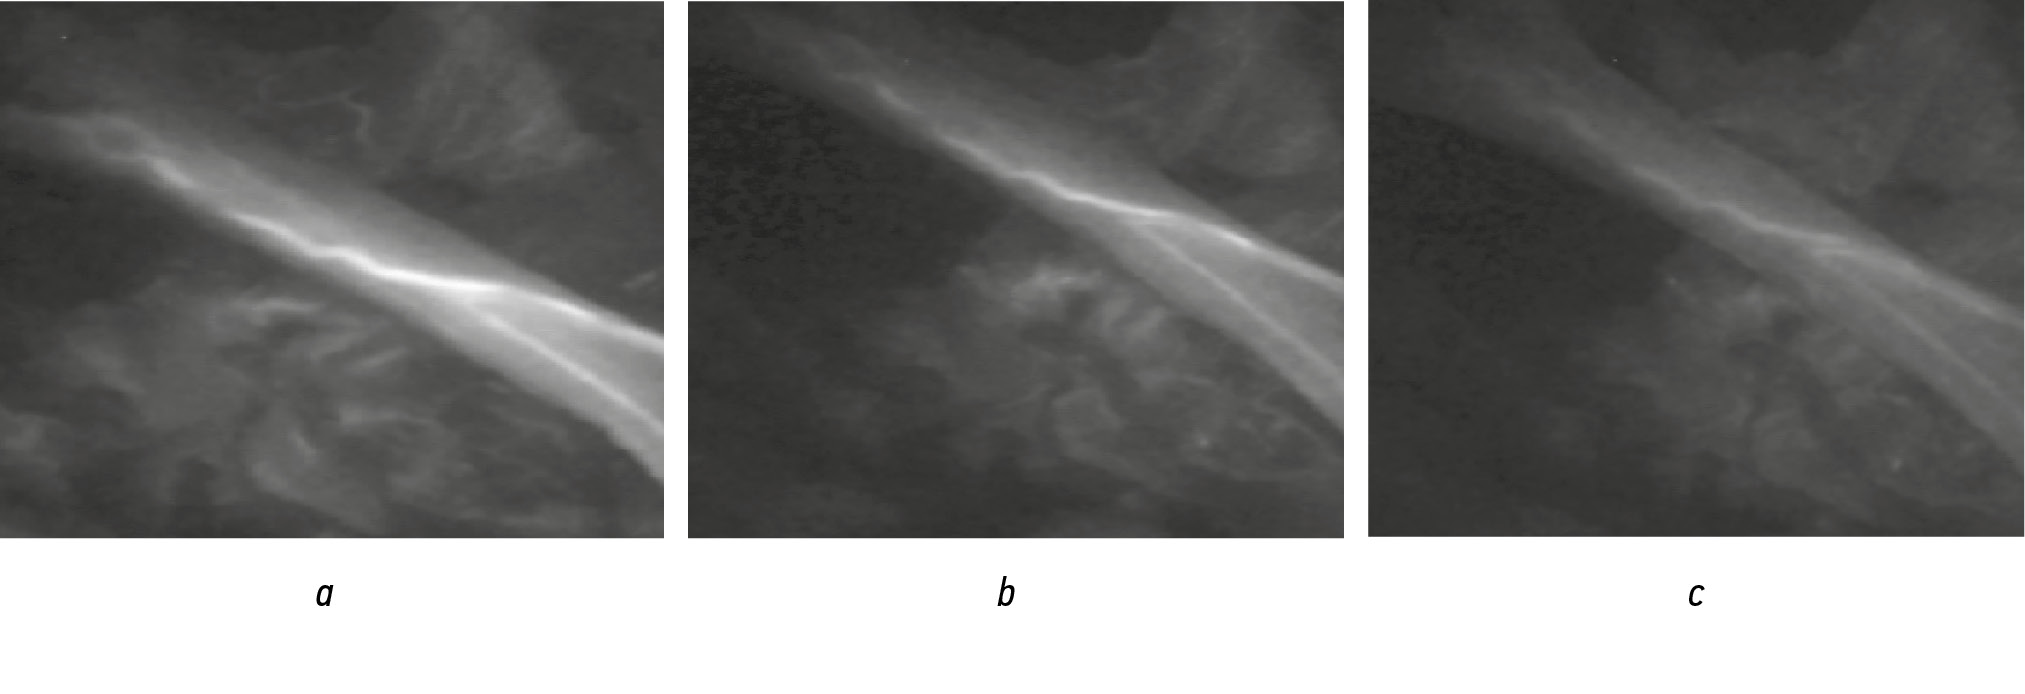

Процедура интраоперационной флуоресцентной ангиографии, включая этап подготовки, занимала около 15 мин. Пациентам, которым выполнялся эпинервальный микрохирургический шов, она была выполнена дважды — во время непосредственного исследования влияния силы натяжения на кровоснабжение и после восстановления целостности нерва. Представленные ИЦЗ-ангиограммы свидетельствуют, что применение интраоперационной флуоресцентной ангиографии позволяет наглядно оценить кровоток в нервном стволе и изменения его при воздействии силы натяжения (рис. 2, 3).

Рис. 2. ИЦЗ-ангиограммы ствола лучевого нерва: а — без воздействия силы натяжения; b — при воздействии силой натяжения в 2 Н; c – при воздействии силы натяжения в 3 Н / Fig. 2.Indocyanine green (ICG)-angiograms of the radial nerve trunk: a — without the influence of the tension force; b — when exposed to a tension force of 2 N; c — when exposed to a tension force of 3 N

Выявлено, что при приложении силы в 2 Н происходит снижение объема кровотока в основном за счет растяжения сосудов и уменьшения их диаметра. При этом сохраняется сниженное, но достаточно интенсивное контрастирование интраневрального магистрального сосуда, визуализируются сосуды мелкого калибра. Однако в сосудах меньшего диаметра отмечается более существенное снижение интенсивности свечения и их выраженная констрикция (см. рис. 2, 3). Приложение силы натяжения влияет также и на ангиоархитектонику нервного ствола. Так, при воздействии с силой в 2–3 Н изменения проявляются в основном в виде вытяжения, выпрямления сосудов по оси и уменьшения их извитости. При приложении силы в 3 Н визуально отмечается существенное снижение объема кровотока. Несмотря на сохраняющееся остаточное контрастирование интраневральной магистральной ветви, отмечается выраженное снижение интенсивности ее окрашивания, уменьшение диаметра. Также прекращается контрастирование большей части мелких по калибру сосудов, что свидетельствует об отсутствии или снижении в них кровотока. При этом после прекращения воздействия силы натяжения моментально отмечается восстановление контрастирования этих сосудов, что свидетельствует о восстановлении кровотока. Таким образом, установлено, что приложение силы до 2 Н существенно не влияет на кровоток. В то же время приложение силы в 3 Н уже значительно отражается на кровоснабжении нервного ствола, что подтверждается данными ИЦЗ-ангиографии. Однако и в этом случае не происходит полного прекращения кровотока. Приложение силы более чем в 3 Н мы не проводили с учетом того, что при воздействии на ствол силой более 3 Н происходит выраженное повреждение ультраструктур нерва [13].